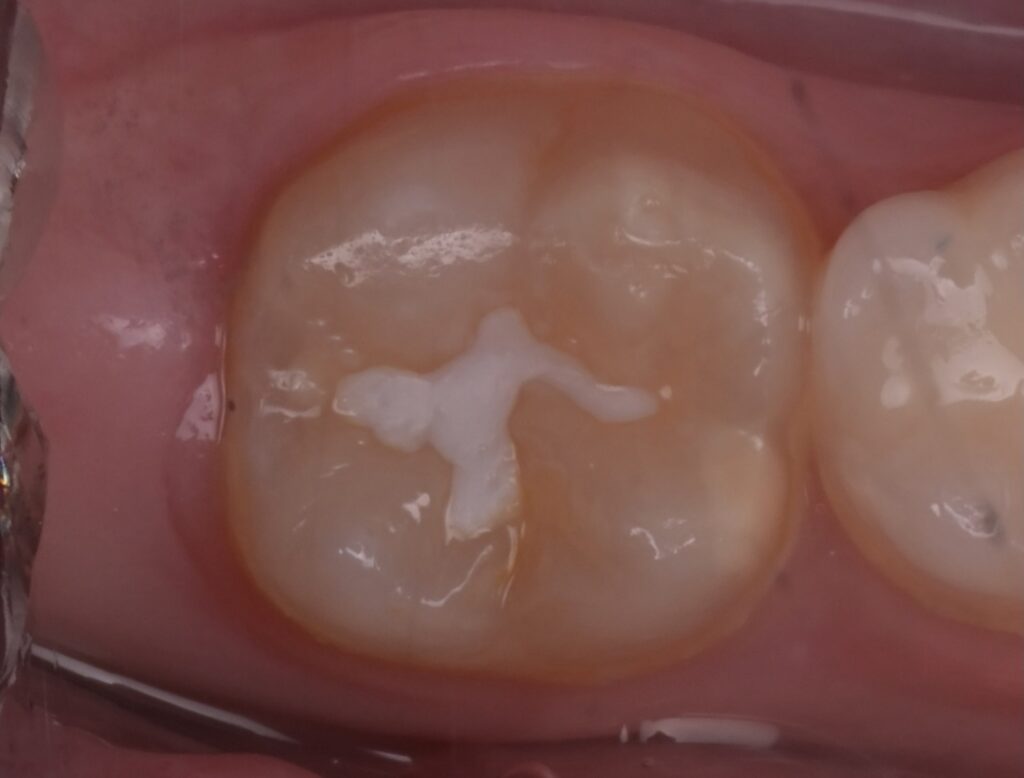

Le sigillature sono un trattamento indolore e sicuro che aiuta a proteggere denti dalla carie, riducendo il rischio di problemi futuri. La sigillatura consiste in uno strato protettivo di resina che viene applicato sui solchi dei molari per impedire l’accumulo di placca e batteri.

Dopo aver pulito il dente con uno spazzolino rotante e una pasta abrasiva, viene applicato sul dente un gel che prepara la superficie del dente. Dopo qualche secondo questo gel viene lavato e il dente asciugato per poter applicare la resina su un dente asciutto. La resina viene poi fatta indurire con una lampada speciale.

Le sigillature si eseguono solamente su denti sani e possono durare diversi anni ma vanno controllate regolarmente dal dentista.